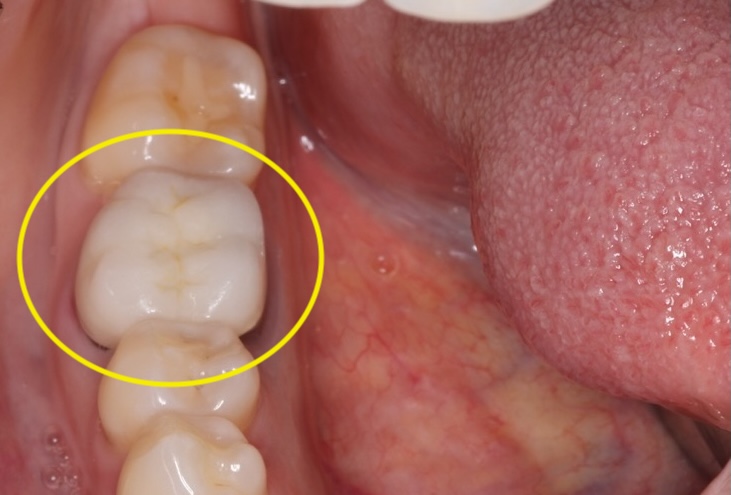

Comprehensive biological oral surgery case showing Tooth #30 extraction, guided bone regeneration, implant placement, and crown restoration using Groton Wellness’ minimally invasive, biologically supportive protocols.

- Biocompatible crown materials with precision occlusion adjustment for comfortable, long-term function.

Jennifer experienced full functional and aesthetic restoration of her molar region with no complications. Her final crown placement integrated seamlessly with her bite, and full chewing function was restored.

This case demonstrates Groton Wellness’ ability to support long-term wellness with biological protocols that respect both oral structures and systemic health.